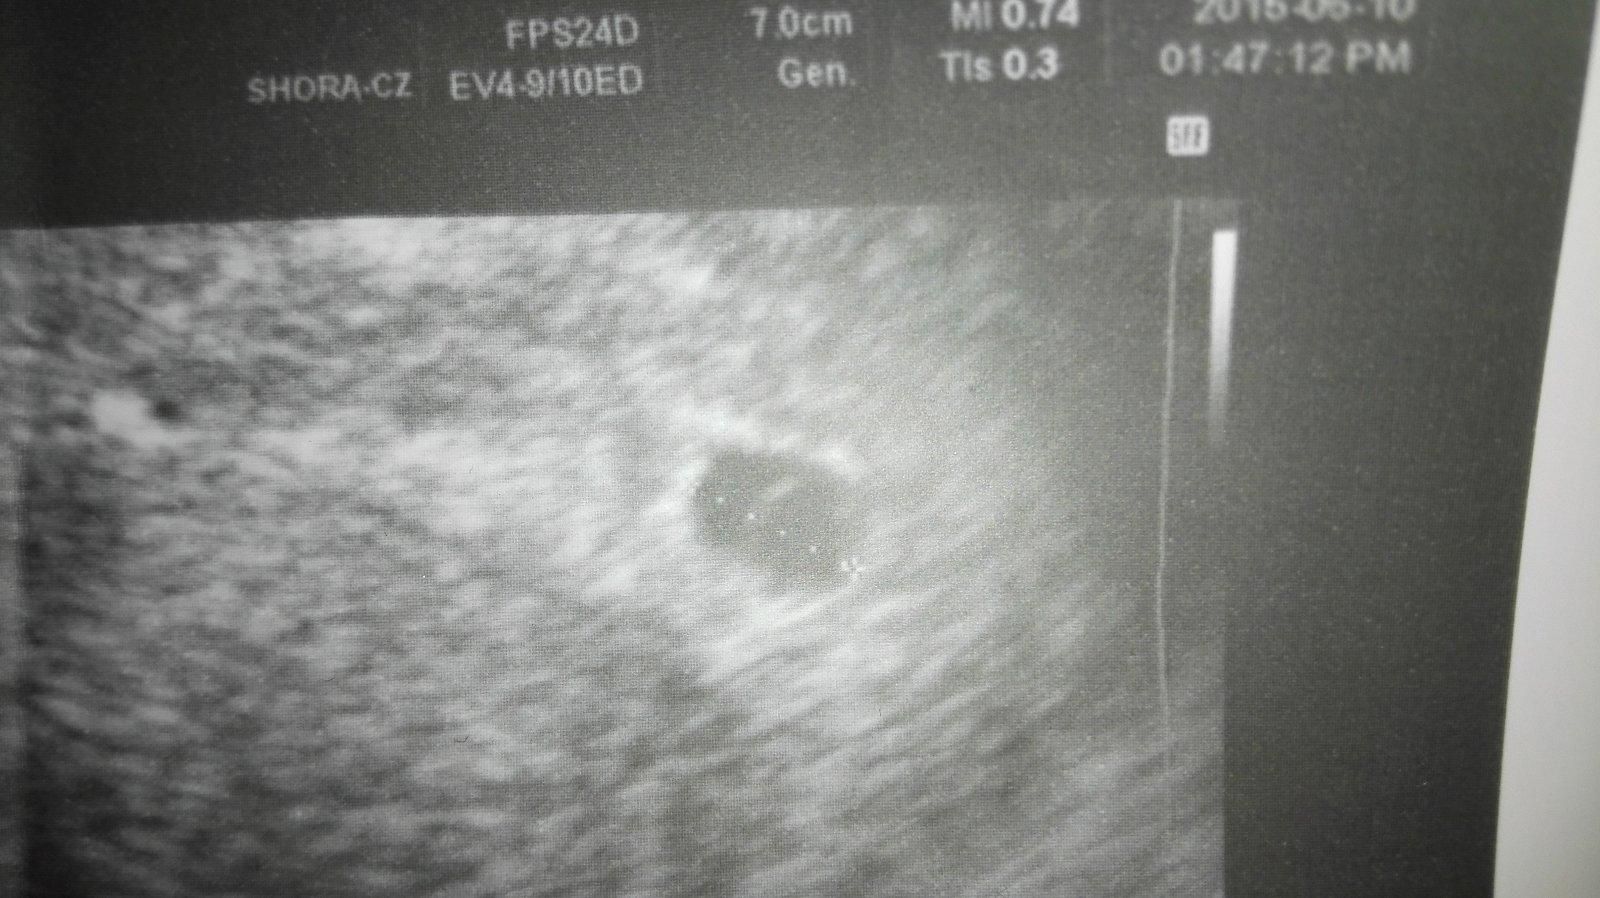

50 den od poslední ms co na utz půjde vidět ( těhotná)

Ahoj chci se zeptat ve středu jdu k doktorovi jsem ten de 50 dni těhotná od poslední ms , ale tak se to asi nepočítá , že ? mimi mělo v pondělí 5 mm no spíš embryo . Měla bych být tedy 7 týdnů??